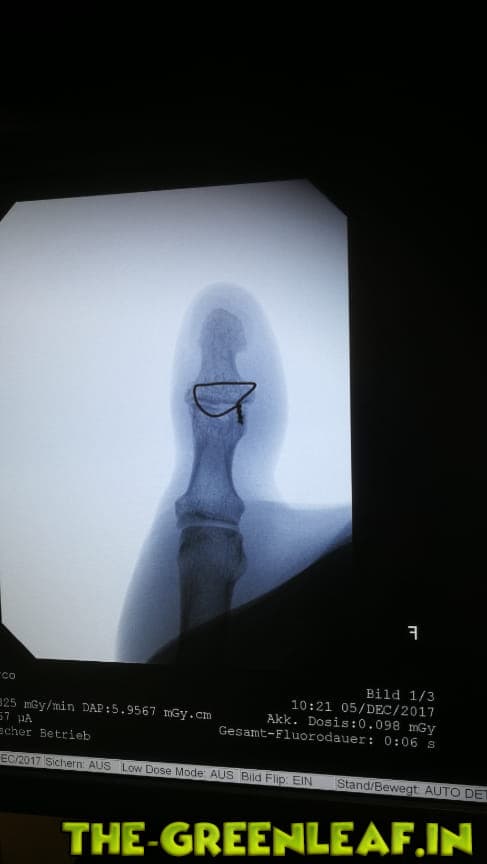

nö Oli nen OP Draht entfernen

Guckst du, so sah das aus.

-

krass... sieht ja aus wie beim Armierung binden

ja.. ganz genau mit sowas werden auch unsere fundamente armiert